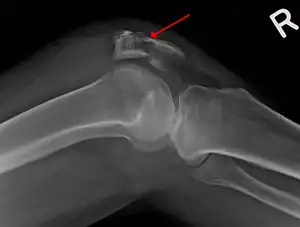

| A fracture of the patella seen on a lateral view | |